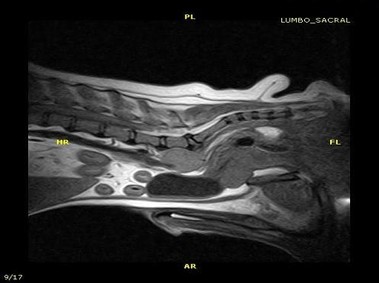

В настоящее время МРТ является наиболее предпочтительным методом визуализации любых мягких тканей, особенно для визуализации травм и патологий центральной нервной системы и суставов. Особенности Vet-MR позволяют использовать данный метод визуализации также в сфере ветеринарии.

Vet-MR специально разработана для визуализации небольших животных и является результатом внимания к деталям при разработке магнита, катушки и электронных компонентов, обеспечивая высокое качество экономически эффективной и простой в использовании МРТ в сфере ветеринарии.

- Высокое качество изображения

- Специальное программное обеспечение, полный набор предварительно установленных последовательностей и протоколов для ветеринарных целей

- Настроенные под пользователя протоколы обследований для специальных клинических потребностей